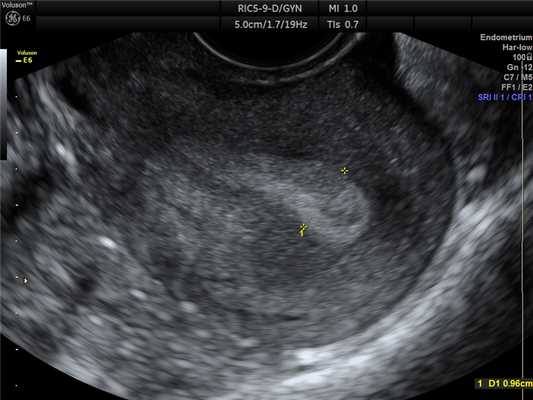

Номальная матка

Рис. 1. Нормальная матка.

Вторая фаза цикла. Миометрий однородный.

Толщина М-ЭХО соответствует дню цикла.

При оценке состояния матки при УЗИ можно определить:

- Положение матки.

В норме матка бывает либо отклонена в сторону мочевого пузыря, то есть кпереди (это положение матки называется anteflexio), либо отклонена в сторону прямой кишки, то есть кзади, - (retroflexio). - Размеры матки (продольный, передне-задний и поперечный). Средние значения размеров нормальной матки в длину от 4,0 до 6,0 см, переднее-заднего от 2,7 до 4,9 мм.Размеры тела матки варьируют в зависимости от возраста женщины, конституции и акушерско-гинекологического анамнеза.

- Состояние эндометрия (его толщина изменяется в зависимости от дня менструального цикла).

Сразу после окончания менструации эндометрий визуализируется в виде полоски толщиной 1-2 мм. Во второй фазе цикла толщина эндометрия (М-ЭХО) может составлять от 10 до 14 мм в среднем. - Состояние миометрия.

В норме миометрий должен быть однородным и не иметь в своей структуре патологических образований (миомы, аденомиоз и т.д.)